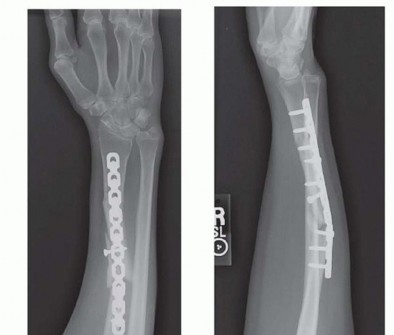

FIG 3 • A,B. AP and lateral radiographs demonstrate a segmental radius shaft fracture resulting in a malunion both proximally and distally despite open reduction and internal fixation. Note the loss of radial bow in both direction and magnitude, narrowing of the interosseous space between the radius and ulna, dorsal positioning of the distal ulna, and nonunion of the basilar ulnar styloid fracture. The patient was unable to supinate to neutral and demonstrated instability at the DRUJ. C. CT scan demonstrates narrowing of the interosseous space with heterotopic bone formation. P.219The degree of angulation and comminution can be calculated from these films.Contralateral forearm films provide a comparison for the amount of shortening as well as for the location and angle of the radial bow. 9A computed tomography (CT) ( FIG 3C) scan or magnetic resonance imaging (MRI) can also be obtained to assess for malrotation.2